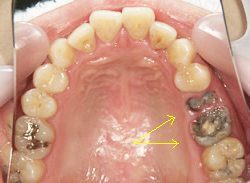

① インプラント

| 治療前 | 治療後 |

主訴 |

インプラントを入れたい |

治療期間 |

8か月 |

治療費 |

インプラント1本¥200,000×3 チタンアバットメント¥50,000×3 メタルセラミックス¥100,000×3 合計¥1,050,000(税別) |

治療内容について |

矢印の歯の虫歯が深く、保存が困難でしたので、抜歯となったケースです。 抜歯をしてから骨と歯肉が十分に治癒するまで5か月ほど待って、インプラントを埋入しました。 インプラント治療をするにあたっては、口腔内の清掃の徹底と、歯周病の基本治療をきちんと済ませることが、インプラントを長持ちさせるためにとても重要となります。 |